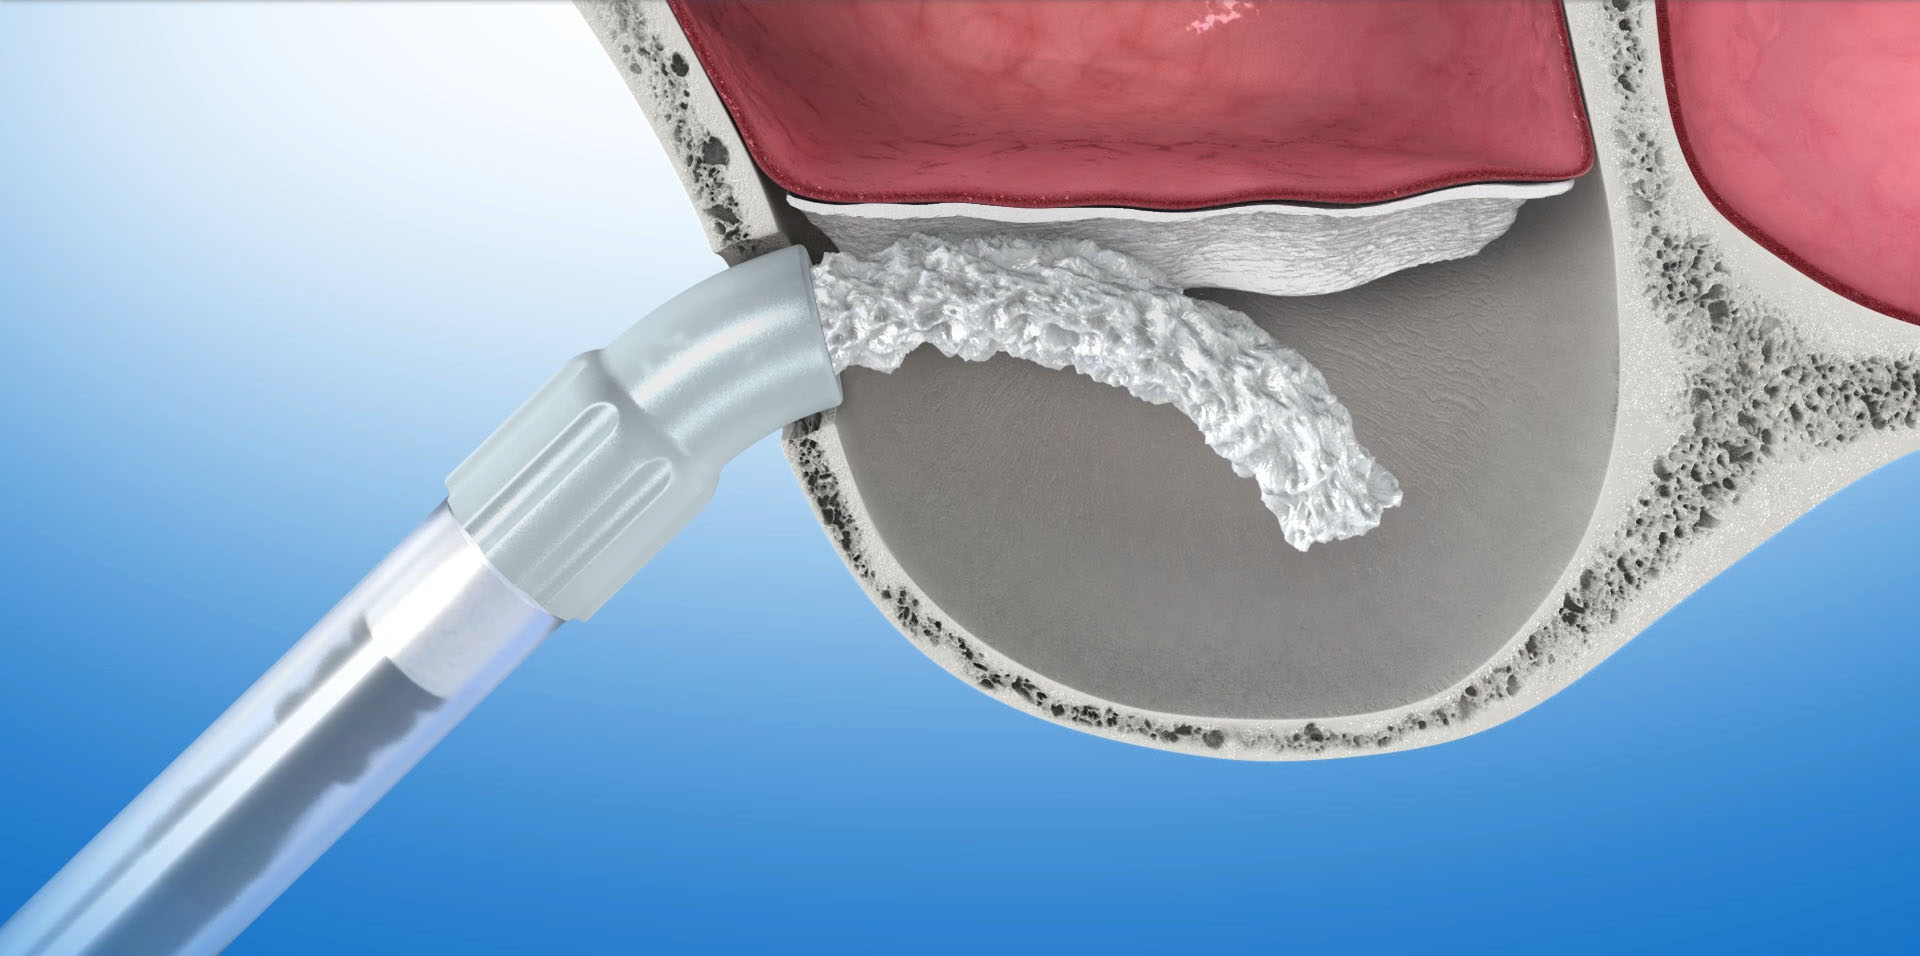

Podniesienie dna zatoki szczękowej metodą otwartą

Polega na wycięciu w bocznej ścianie zatoki małego okienka, przez które narzędziami ultradźwiękowymi i ręcznymi delikatnie odwarstwiamy błonę śluzową zatoki od kości dna zatoki. W uzyskaną przestrzeń aplikujemy materiał kościotwórczy. Okienko pokrywamy membraną zaporowa i zamykamy dostęp do zatoki. Tą metodą możemy uzyskać nawet ponad 10mm nowej kości, która umożliwi nam implantację w tym obszarze. Po zabiegu następuje okres regeneracji kości, w czasie którego wprowadzony biomateriał zamienia się w tkankę kostną. W zależności od ilości użytego biomateriału i stopnia podniesienia dna zatoki okres ten może trwać od 6 do 12 miesięcy.